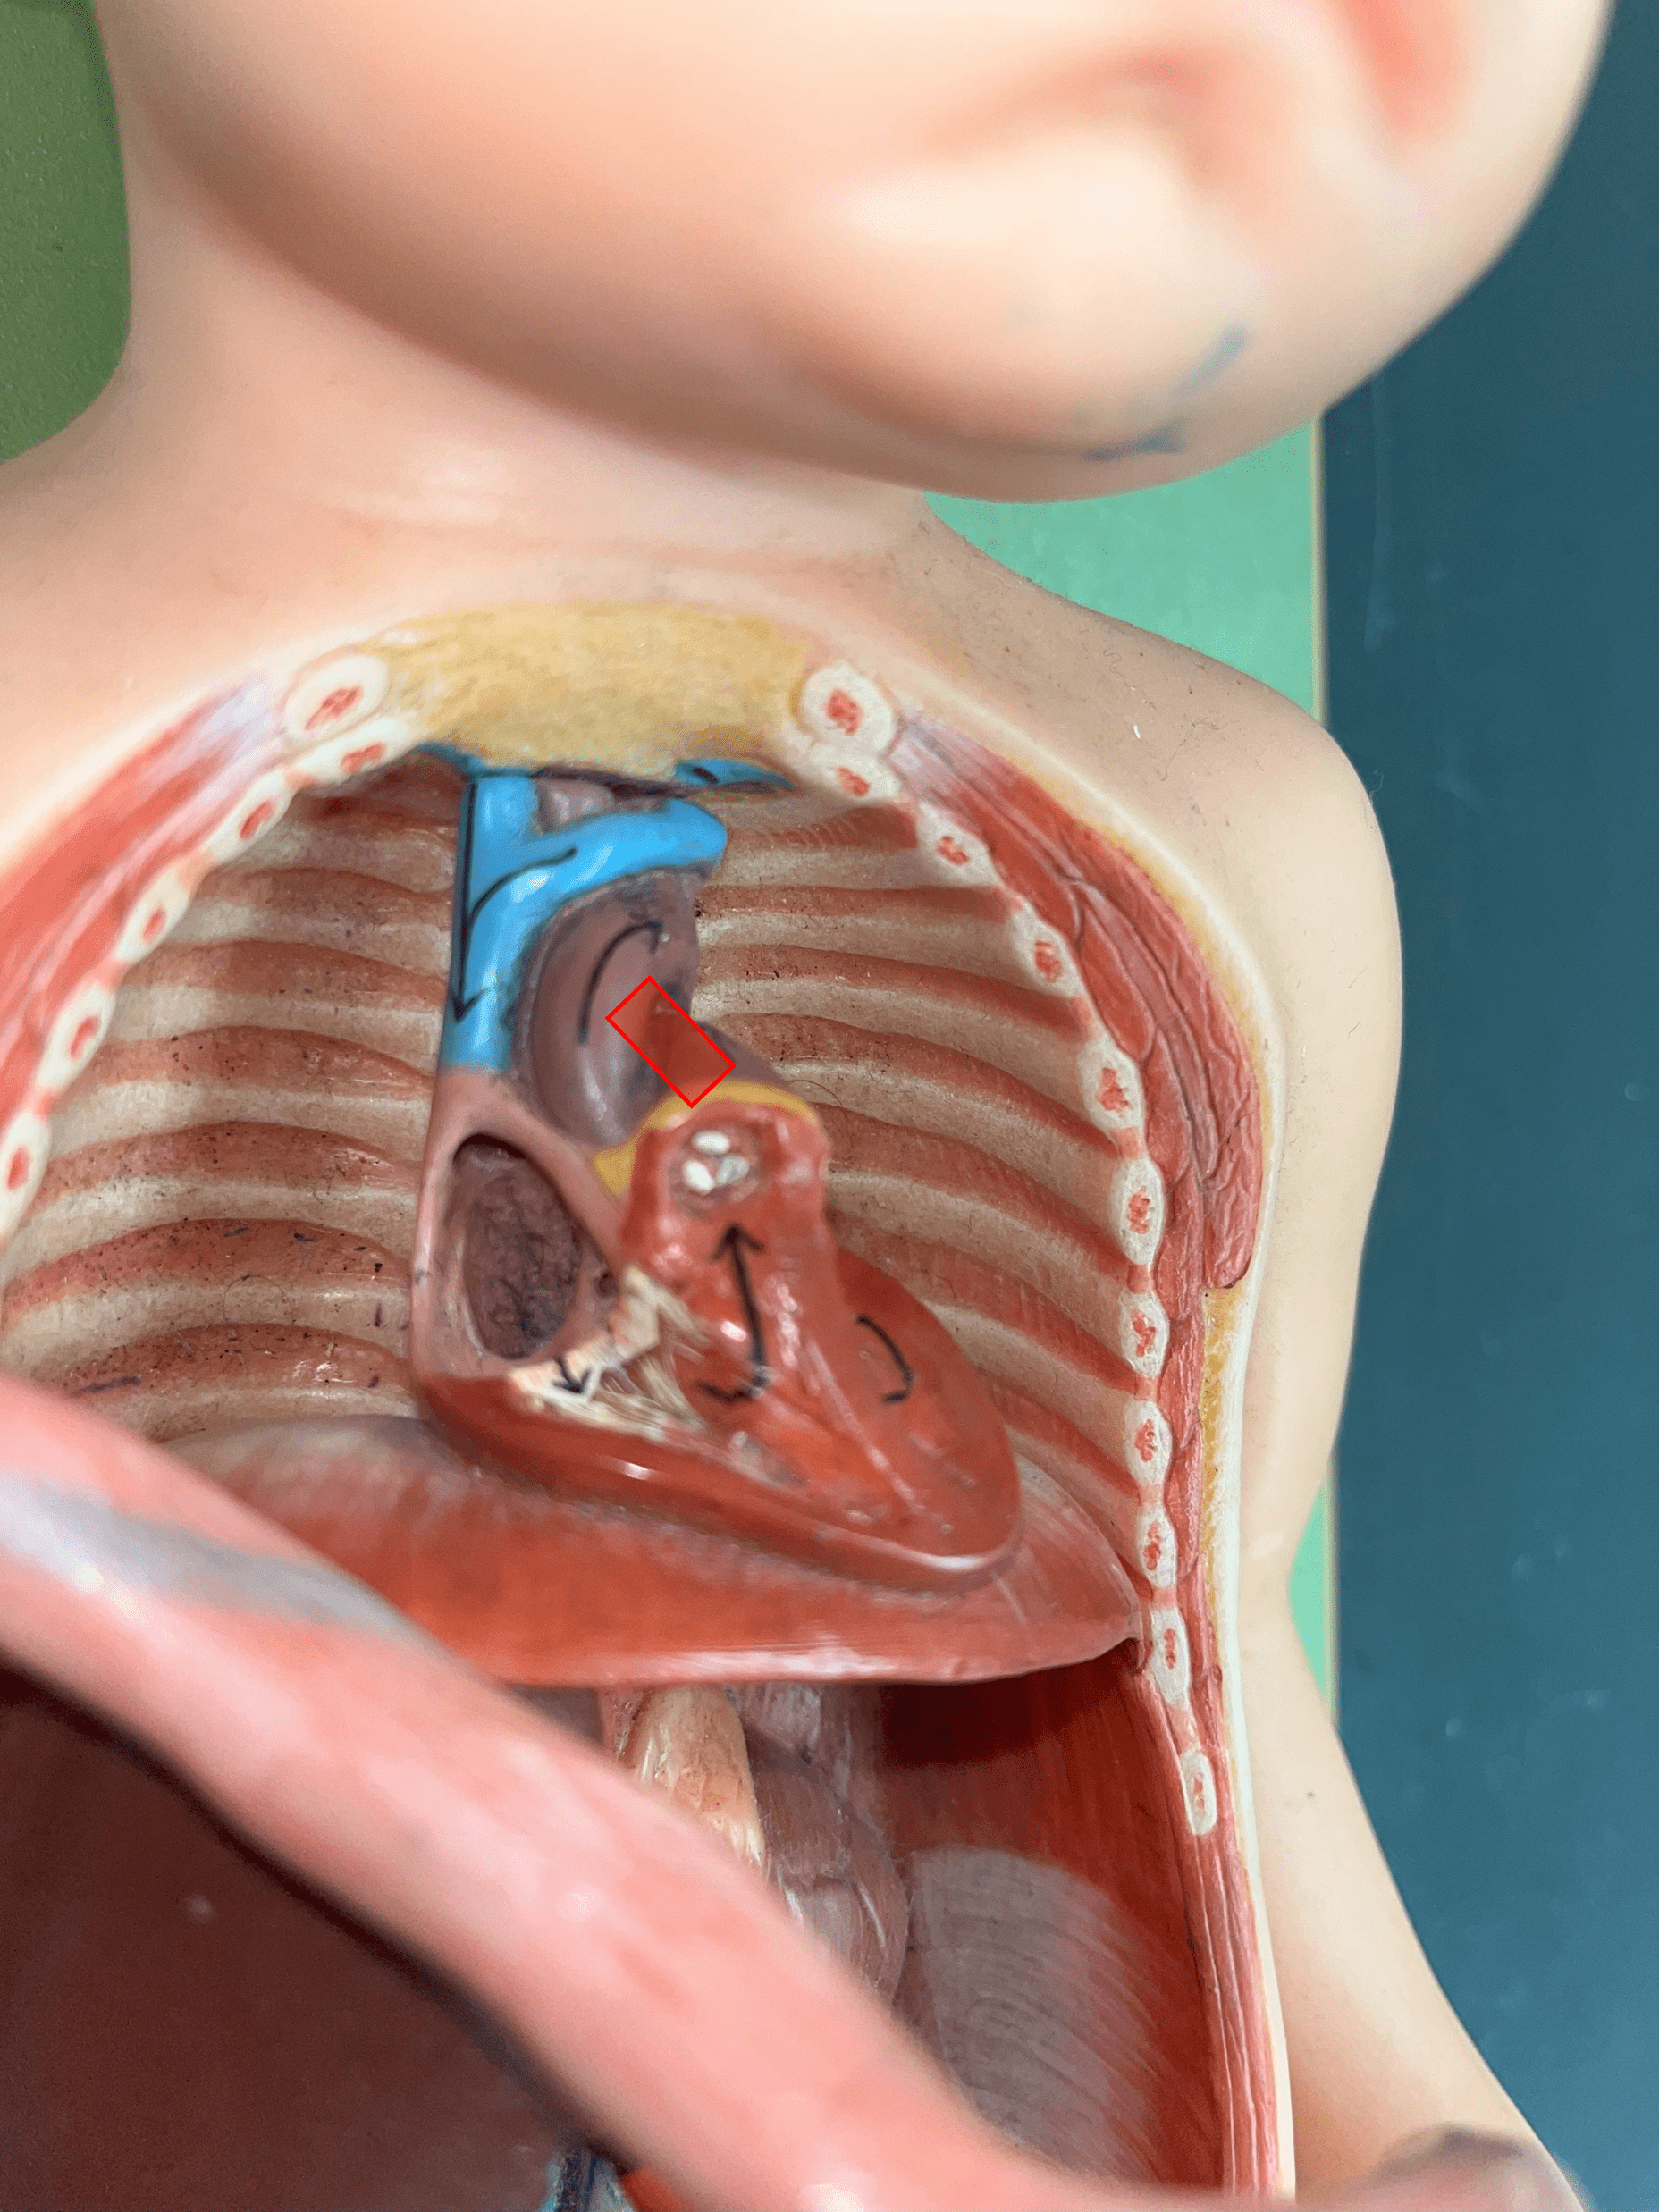

ductus arteriosus

• Part of the fetal circulation.

• Shortcuts blood from the pulmonary trunk to the aorta, bypassing the pulmonary circuit.

• Becomes the ligamentum arteriosum.

• Shortcuts blood from the pulmonary trunk to the aorta, bypassing the pulmonary circuit.

• Becomes the ligamentum arteriosum.